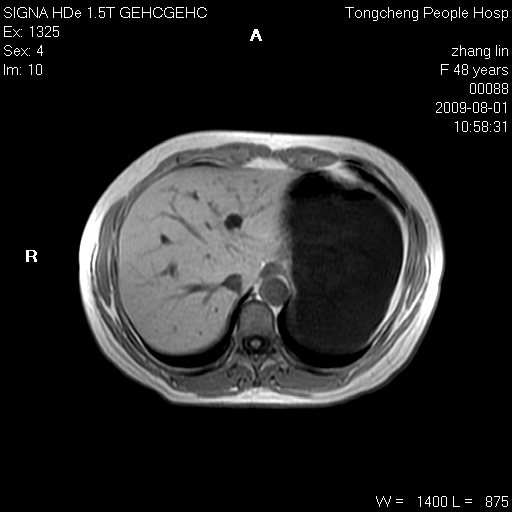

女,48岁。健康体检,彩超发现右肾占位性病变。平素健康。

临床诊断:右肾占位性病变,性质待定(囊肿?肿瘤?)。

上中腹部mr平扫+增强扫描,图像如下:

肝囊肿